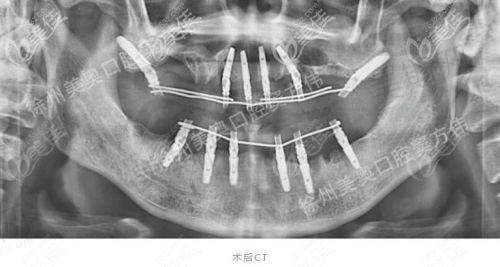

設備要先進:要有CBCT三維掃描儀(香港诊所基本都有,但深圳部分細诊所仲用傳統X光,唔夠精準),3D導板種植(減少手術風險);

植牙技術:穿顴穿翼全口,香港價格(HKD):35萬 - 60萬,適合人群:牙槽骨嚴重吸收、無法植骨嘅長輩,特點:直接打釘入顴骨,唔使植骨,手術難度高

住元朗嘅陳太(湊兩個仔嘅媽咪)就試過深圳種牙:「香港診所話我牙槽骨薄,要植骨再加All - on - 6,總共32萬HKD,仲要分6次醫生,我帶住兩個細路根本冇時間!後來聽朋友介紹去福田口岸附近間诊所,有香港醫生駐場,做穿顴穿翼全口,連埋來回車費同檢查,先25萬HKD,兩日搞掂,返到香港第二日就返學接仔,食飯終於唔使『捱粥』!」